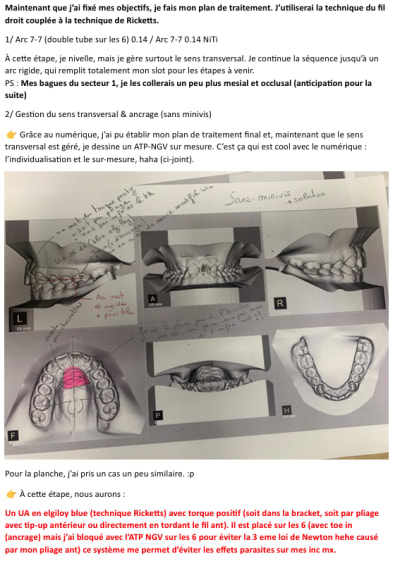

Salut Dancha, désolé pour le pavé et les erreurs. J’ai préféré le faire en doc, c’est plus fluide. ^^

J'espère que les images sont dans l'ordre ^^

Excellente analyse qui propose même avec beaucoup de détails plusieurs solutions ! C'est très intéressant et ça montre que l'orthodontie n'est pas toujours aussi simple qu'on pourrait le croire quand on écoute le discours de certains fabricants de gouttières.

Avant que je montre moi-même l'approche encore différente que j'ai choisie (😊) pour traiter ce cas, pourrais-tu nous dire exactement où tu placerais une vis pour bloquer 21 et 23 ? Et comment une simple ligature en 8 pourrait être suffisante, sans risque de générer une composante verticale délétère ?

Étape 1 (photo Figure 1)

1. Arc SS ou TMA 7-7 en 18x25, avec une ligature en 8 de 11 à 26, un peu lâche, car je veux profiter des effets parasites sans créer de déviation maxillaire. En général, cela suffit pour cet objectif.

2. Minivis de 1,5 mm de diamètre et 6 mm de longueur (plus proche de la racine de 11)

3. Bras en Blue Elgiloy 18x25, avec double boucle côté intérieur. La partie horizontale doit être 1,15 fois plus grande que l’espace à fermer entre la canine et l’incisive. J’ajoute une gaine en plastique dessus pour éviter de blesser le patient.

4. Ligature en 8, car même si les effets parasites ne m’inquiètent plus face au risque d’AI, au pire, je risque peu de proversion coronaire → pseudo-ingression → accentuation de l’infra. Je temporise ces effets au maxx avec la ligature et les corrigerai par la suite a l’etape 2 avec les effets parasites contraires (Les mouvements de va-et-vient sont déconseillés, mais ici, ils seront négligeables.)

Etape 2 (photo figure 2) : Une fois la mésialisation de la canine faites le plus dure, je fais la mésialisation de mon bloc lat classique ou j’ai justement du recul